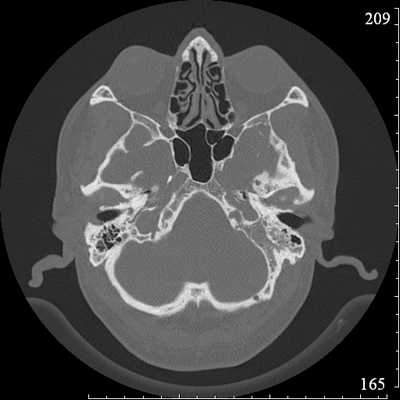

Во время КТ получают послойные снимки височной кости и окружающих тканей в трех плоскостях. Толщина среза составляет всего несколько миллиметров, что позволяет врачу-рентгенологу рассмотреть не только все анатомические образования, но и минимальные патологические изменения.

На полученных снимках хорошо видны следующие структуры:

пирамида височной кости;

ячейки и антрум сосцевидного отростка;

улитка, преддверие, передний и задний полукружный каналы;

слуховые косточки среднего уха;

стенки наружного слухового прохода;

Снимок (томограмма) височных костей в осевой проекции